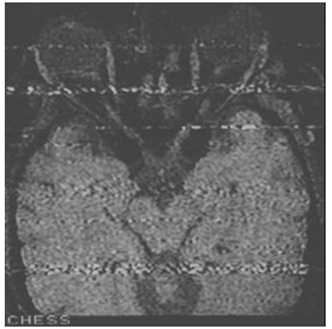

Os artefatos podem ser originários do magneto, do gradiente de

campo magnético, do sistema de radiofrequência, da técnica de

aquisição, do paciente ou de componentes externos ao aparelho.

Acerca do item, observe a imagem a seguir.

A imagem descreve um artefato